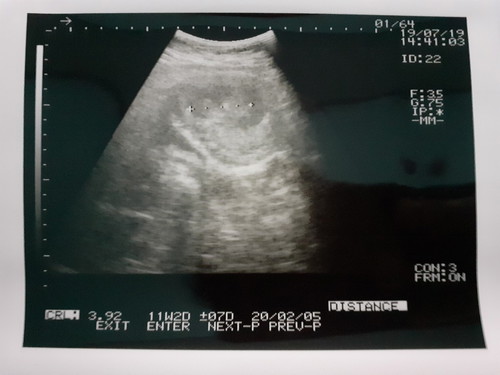

USG

Bun mau sharing, ini usg saya hari jumat 19 juli kemarin, kalau usia dr bisan 12 minggu lebih 2 hari tapi pas usg 11 minggu lebih sekian hari. Trs kata dokter janin saya ukurannya kurang, saya sudah berusaha makan dan minum walaupun mual mutah tetep saya paksa. Sudah minum susu bum walaupun 1 hari 1x lalu minum asam folat dan vitamin. Kata dokter suruh makan yg banyak aja. Tapi saya takut bun kalau janin saya knp2 ?. Menurut bunda apa yg harus saya lakukan, karena ini anak pertama bun, masih kurang pengalaman ?